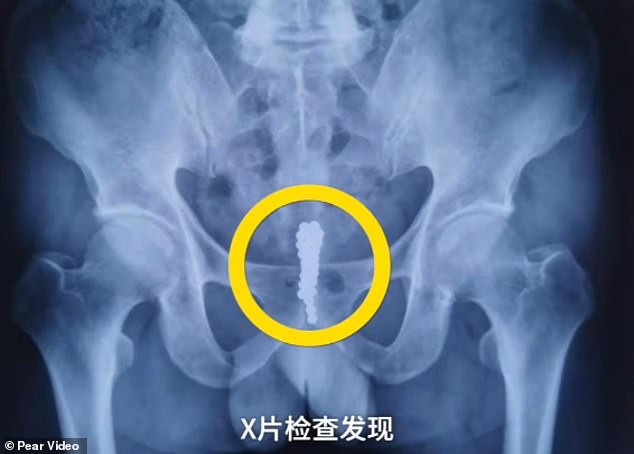

Trung Quốc: Người đàn ông nhét 28 viên bi nam châm vào niệu đạo ảnh 1Kết quả chụp X-quang cho thấy một chuỗi hạt trong bàng quan của bệnh nhân. (Nguồn: Pear Video)

Người đàn ông 58 tuổi này đã nhập viện vì bị bí tiểu. Ban đầu, ông cho biết đã nhét một viên bi nam châm vào niệu đạo. Tuy nhiên, sau khi chụp X-quang, các bác sỹ phát hiện không chỉ là 1 viên bi mà là cả một chuỗi dài trong niệu đạo.